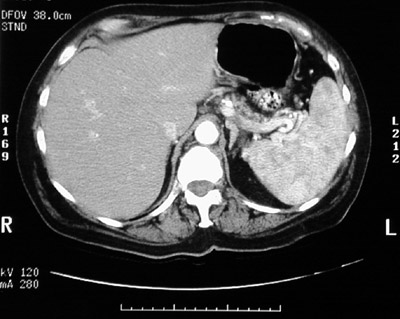

The heterogenous areas of brightness within the normal-sized spleen here are not due to a disease process, but represent an artefact that can be seen with the phase of arterial uptake of contrast material during the CT procedure.